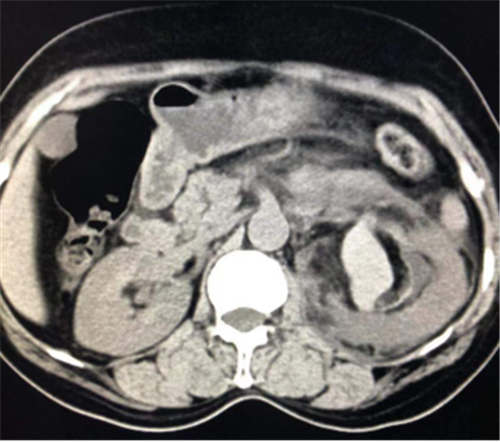

患者邓某,女,54岁,因突发左侧腰部疼痛1天入住小艾电竞社区 普胸泌尿外科,经增强CT检查诊断为左肾血管平滑肌脂肪瘤伴出血。为止血及切除肿瘤,因传统的开腹手术创伤大,术后恢复慢,而微创介入手术相对止血较彻底,创伤小,普胸泌尿外科决定由放射科实施左肾肿瘤栓塞术。术后患者血管减影出血停止,肿瘤栓塞成功,患者病情稳定,病人无需再行外科手术。

此栓塞法即可治疗肿瘤破裂出血,又可使肿瘤完全栓塞,因此为安全、微创、治疗破裂出血的有效方式。